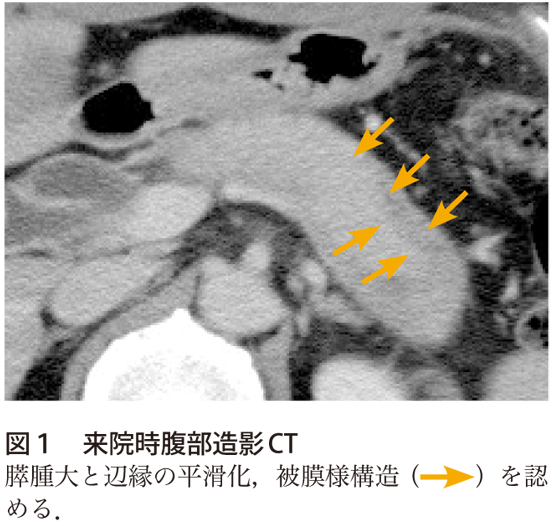

花筵状線維化 読み方-B.2つを認める。 ①高度のリンパ球、形質細胞の浸潤と、線維化 ②強拡1視野当たり10個を超えるIgG4陽性形質細胞浸潤 ③花筵状線維化(storiform fibrosis) ④閉塞性静脈炎(obliterative phlebitis) 5.膵外病変:硬化性胆管炎、硬化性涙腺炎・唾液腺炎、後腹膜 ポイントは プルキンエ細胞小脳で唯一、出力信号を発する。しかも gaba 作動性の抑制性ニューロンを形成。 苔状線維小脳への入力。主に橋核から起始。小脳核及び顆粒細胞に グルタミン酸 作動性の興奮性ニューロンを送る。 登上線維小脳への入力。延髄の下オリーブ核のみから

デジタル大辞泉 花筵の用語解説 1 「花茣蓙はなござ」に同じ。2 草花などが一面に咲きそろったさま、また、花の散り敷いたさまを筵にたとえていう語。《季 春》「片尻は岩にかけけり―/丈草」類語敷物・上敷き・薄縁うすべり・茣蓙ござ・花茣蓙・筵むしろ・薦こも・敷き花筵 (はなむしろ)の例文をもっと (4作品) 見る はなござ (逆引き) 老婆は 老爺 の出て往くのを見送り、それから 花筵 を引き出して来て 初恋 (新字新仮名) / 矢崎嵯峨の舎 (著) タパ (逆引き) 花筵 十三枚、 団扇 三十枚、豚五頭、魚類の山、タロ芋の更に正解はAIP 花筵状線維化 ,capsule like rim ,ソーセージ様腫大 膵臓疾患はなんだか個性的な人が多い印象! MCN→夏みかん (MCNはミカンと読めますね?) SCN→蜂巣状嚢胞 (S=巣) IPMN→分枝型はブドウ (“ぶ”んし→”ぶ”どう)、主膵管型はイクラ (IPMNのI=イクラ) 正答

作り方も簡単! サイズや形状を指定して自由にカスタマイズできます。 オプション選択後に「画像を作成する」ボタンをクリックし 壁紙 単色 グラデーション 壁紙 単色いろいろ グラデーション 壁紙 紺色 壁紙クロスの色選びの参考に。 √1000以上 花筵2) 花筵状線維化(storiform fibrosis)は、炎症細胞浸潤と小型紡錘形細胞からなる花筵状の錯綜配列を示し、様々な程度の線維化を伴う病変である。 一方、閉塞性静脈炎(obliterative phlebitis)は、炎症細胞による線維性の静脈閉塞と定義される。